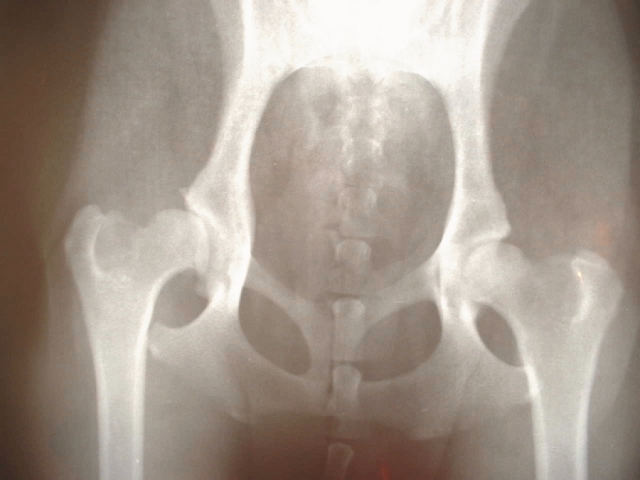

股関節は体の深い部分にあるため、外から見たり触れたりするだけでは状態を正確に把握することが難しいのです。変形性股関節症の診断では、レントゲン検査が最も基本となります。関節がどれくらい変形しているのか、軟骨がすり減っているかなどを客観的に評価できるため、ほとんどの場合はレントゲンだけで診断がつきます。

骨はX線を通しにくいため画像では白く映り、骨の形や位置関係がはっきりとわかります。特に株関節の場合、立った状態で撮影することで体重がかかった時の骨の様子も評価でき、より実際の負荷状況に近い判断ができます。

標準的な撮影方法としては、前後方向と側面方向のX線画像を撮ります。患者さんには仰向けになってまっすぐ寝ていただく形が一般的で、両方の股関節を正面から撮影することで左右の状態を比較できます。また必要に応じてラウエンシュタイン像という特殊な角度からの撮影も行われます。

股関節のレントゲン画像を見るときに、まず注目するのが関節裂隙の状態です。裂隙とは骨と骨の間に見える黒い隙間のことで、正常な状態であればこの部分に軟骨があってクッションの役割を果たしています。ところが変形性股関節症が進むと軟骨がすり減るため、レントゲン上では骨同士が近づいて見え、隙間が狭まっていくのがわかります。

この変化は初期から中期にかけて徐々に進行していくとされており、関節のどの部分が狭くなっているかで負荷のかかり方も推測できます。歩くときに引っかかるような感覚があったり、動かしづらさを感じたりする場合、こうした裂隙の狭小化が起きている可能性も考えられます。